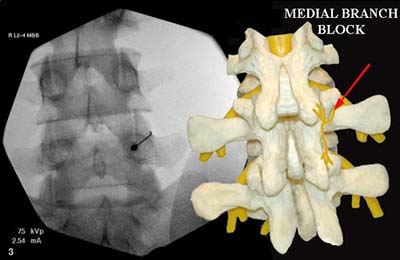

Facet Joint Injection | Barr CenterIf these techniques do not bring about the desired pain relief, we may perform a facet joint injection, which delivers a steroid or anesthetic to reduce inflammation and pain. It will also help to better diagnose the problem. We may also recommend other types of procedures such as medial branch blocks (diagnostic only) or prolotherapy.

If the facet joint injection provides temporary but not long-lasting relief, your physician may discuss the option of radiofrequency Facet Joint Injection Causes (lesioning) of the small nerves, which provide nerve impulses to the facet joints believed to cause your pain.